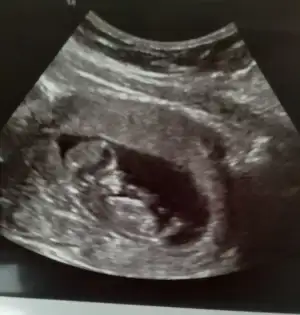

12+1 haftalık acaba bana da cinsiyet tahmini yapar mısınız